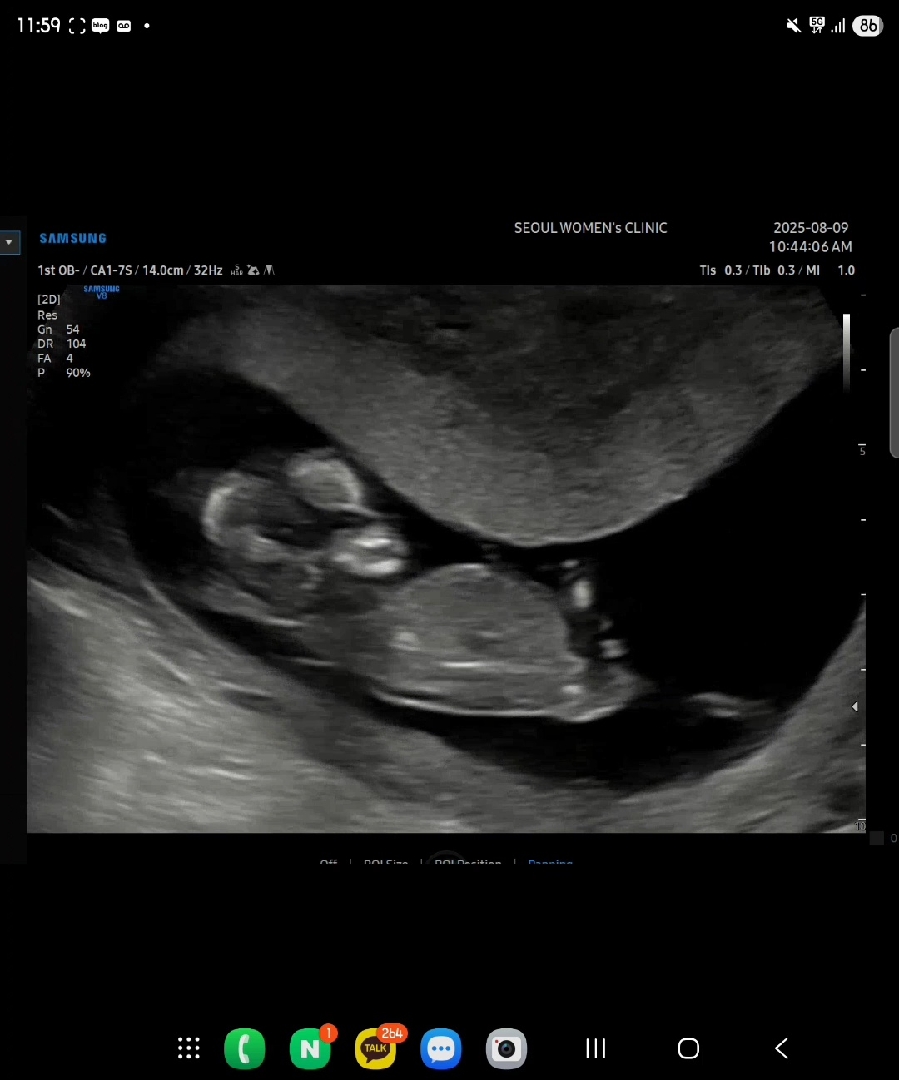

각도법고슈님들 성별뭘까용 12주차1일이욤